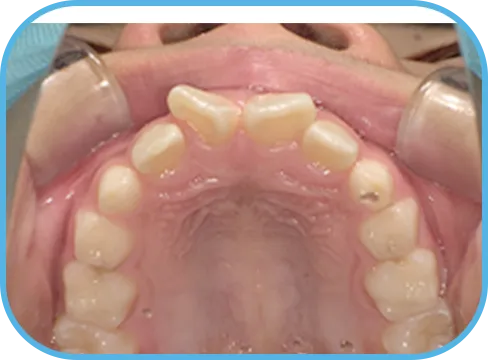

• Before

• 上 顎

治療前上顎からの歯の様子

主 訴

上の前歯がねじれている、ガタガタ

治療内容

インビザライン・ファースト

治療期間

8か月

治療費(税別)

450,000円+診断料50,000円

リスク・副作用

• 親知らずの影響や加齢などによって、凸凹が生じる可能性があります。

• 治療の初期段階では痛みや不快感が生じやすくなりますが、1週間前後で慣れます。

• 顎の成長発育によって、噛み合わせや歯並びが変化する可能性があります。

• 状況により当初予定した治療計画を変更する可能性があります。